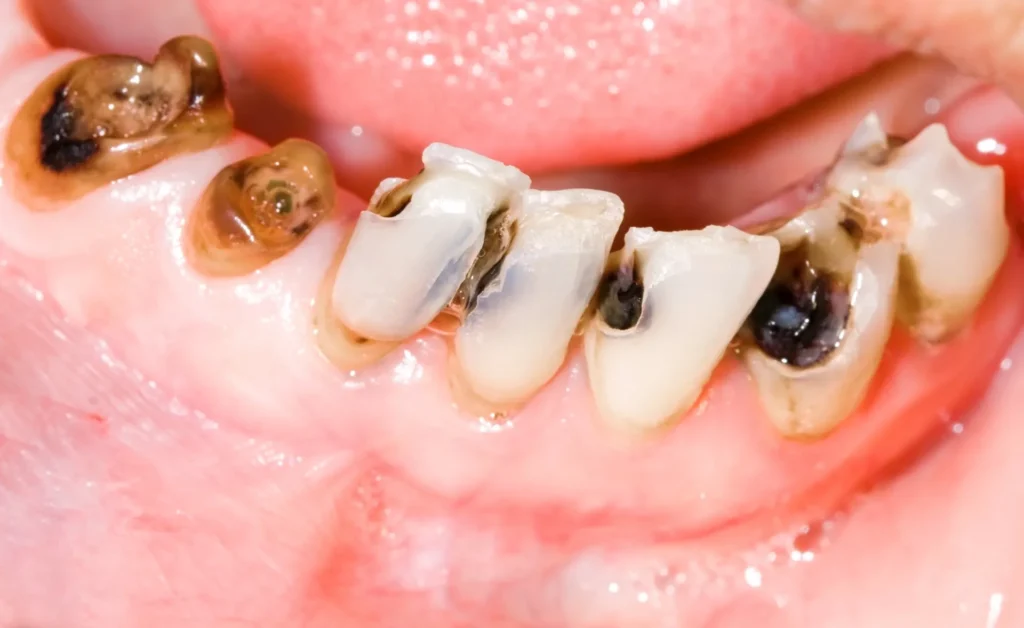

🔹 Viêm tủy hoại tử

Đây là giai đoạn nặng nhất của viêm tủy răng, khi mô tủy đã bị chết hoàn toàn do nhiễm trùng kéo dài.

Biểu hiện:

- Cơn đau dữ dội trước đó có thể giảm hoặc mất hẳn, do các dây thần kinh trong tủy đã hoại tử; tuy nhiên người bệnh vẫn có thể cảm thấy cảm giác nặng, căng tức hoặc khó chịu ở vùng răng tổn thương.

- Hơi thở có mùi hôi, do vi khuẩn và sản phẩm phân hủy từ mô tủy hoại tử.

- Dịch nhiễm trùng từ ống tủy có thể lan qua chóp răng, gây viêm mô quanh chóp, áp-xe răng hoặc sưng đau vùng nướu.

Nguy cơ nếu không điều trị kịp thời:

- Viêm quanh chóp răng mạn tính, phá hủy xương ổ răng.

- Tiêu xương, tiêu chân răng, làm răng yếu dần.

- Mất răng và nguy cơ nhiễm trùng lan rộng sang các mô lân cận.